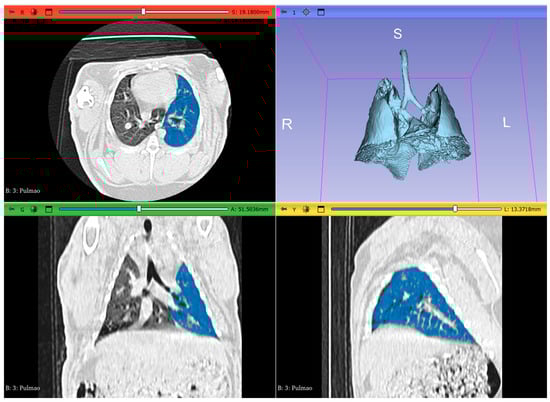

2.3. Image Analysis and Segmentation